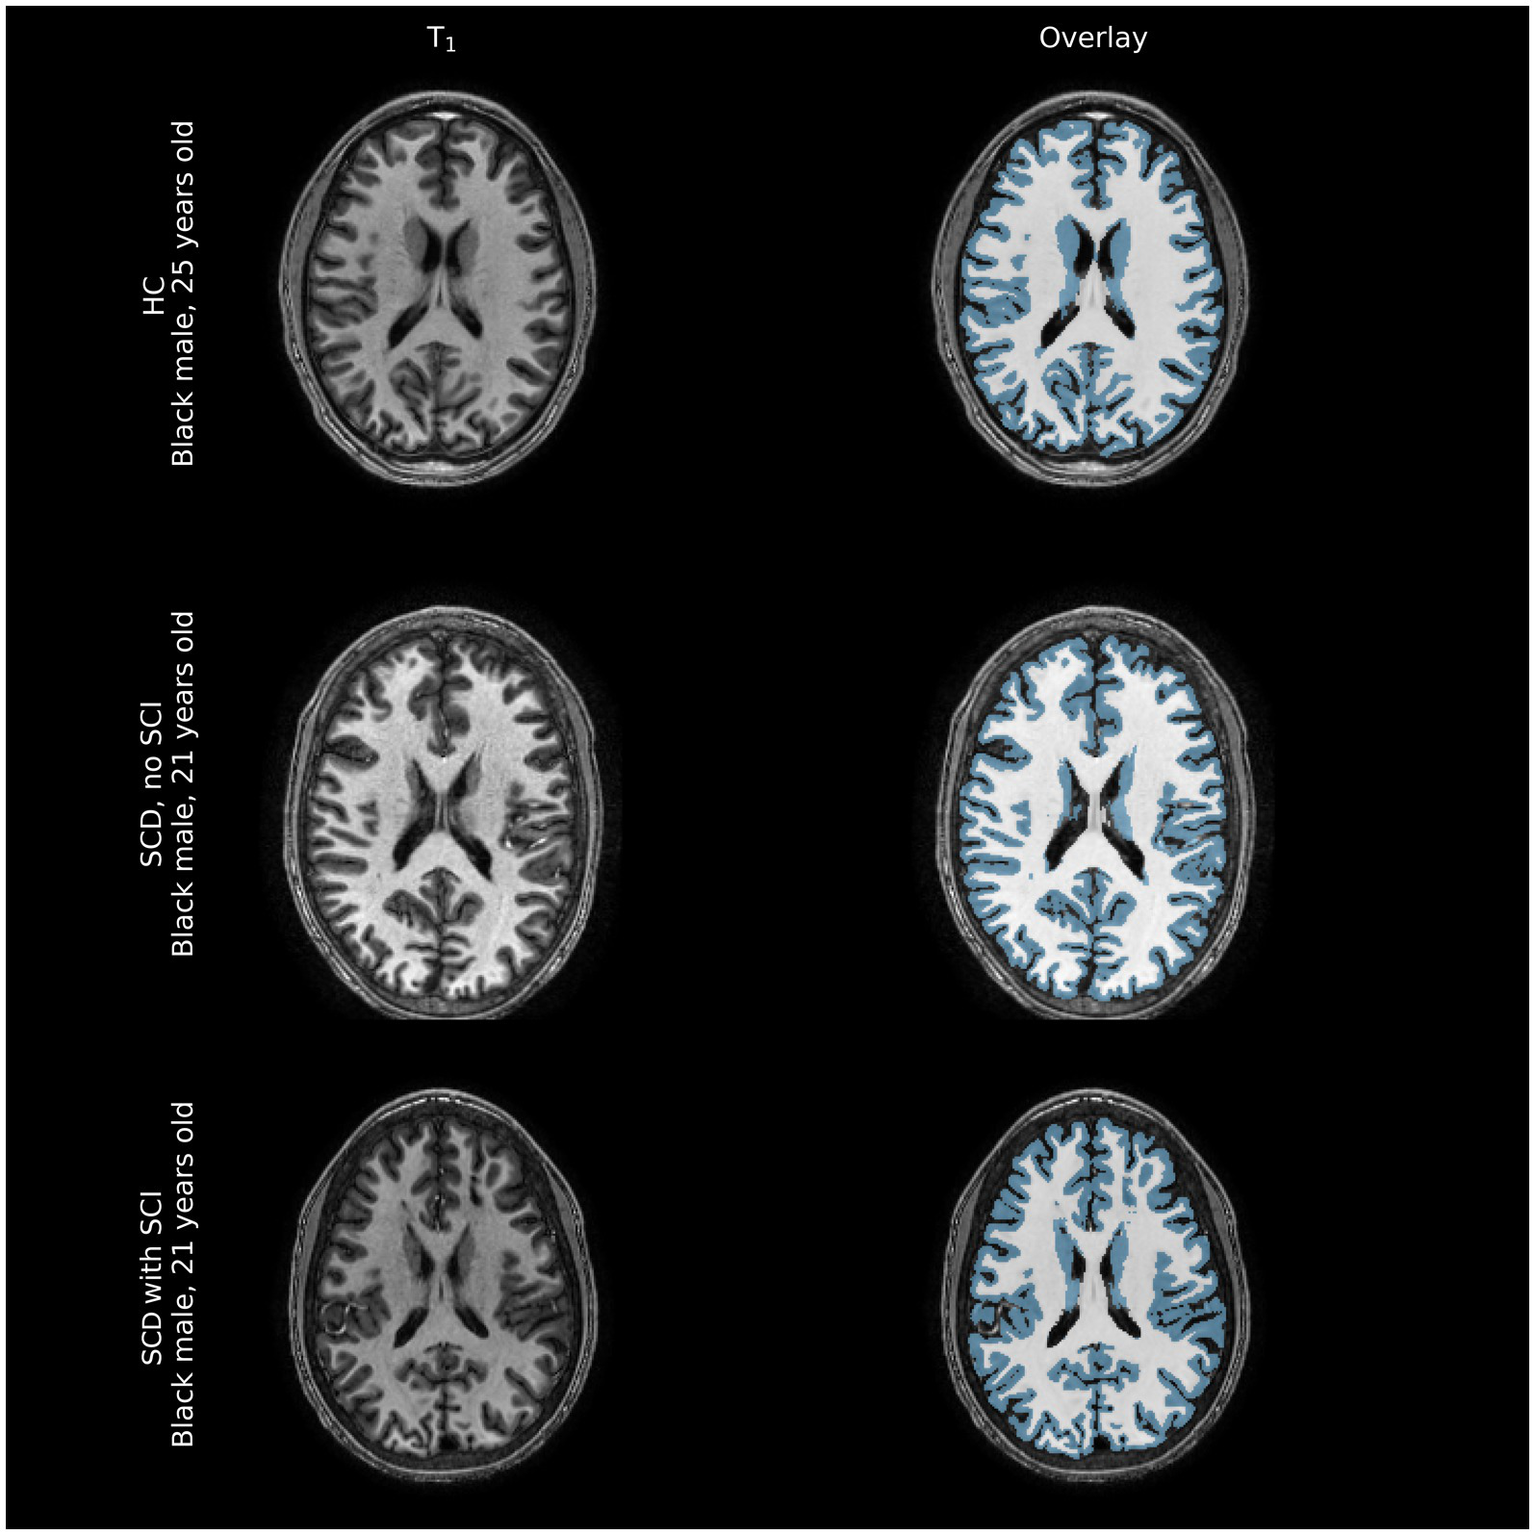

Representative comparisons of anatomical images of individuals with and without SCD, along with their FreeSurfer-derived GM and WM segmentations can be seen in Figure 2, demonstrating the quality of the segmentation as well as the minimal differences apparent on standard anatomic neuroimaging in participants with SCD with and without infarcts and healthy controls. Regression plots of total brain volume against factors hypothesized to impact brain size (SCD presence, hemoglobin and infarct burden) are presented in Figure 3.

Figure 2

Representative comparison of structural images of participant brains along with FreeSurfer-derived gray and white matter segmentations (blue overlay and white overlay, respectively). Tissue volume differences between healthy controls (HC) and individuals with sickle cell disease (SCD) with and without silent cerebral infarcts (SCI) are often not immediately apparent on structural imaging modalities, barring large overt ischemic strokes that were excluded from this sample.